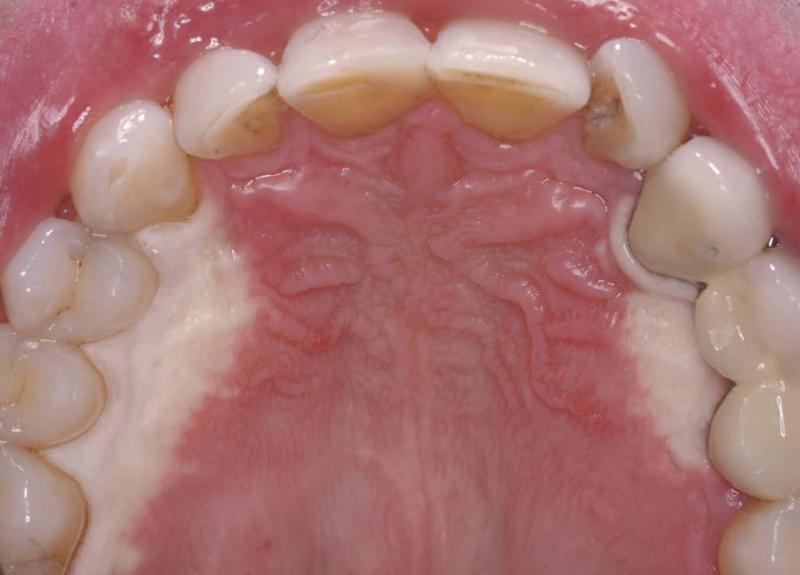

Fibromatosis gingival, (fibromatosis del paladar)